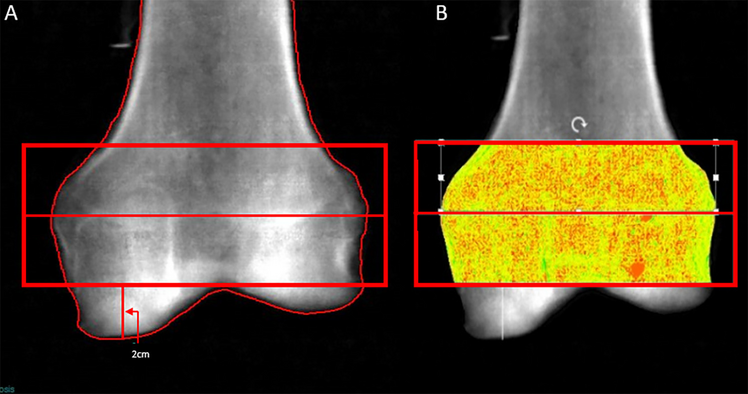

Custom regions of interest (ROIs), 2 cm in height were manually placed using index lines to measure the distance at defined locations along the distal femur (Fig. 4). The areas were again chosen to simulate the location of screw clusters. TBSortho was determined within these same ROIs using the TRIP software version 1.0.1.23.

Fig. 4

DXA (A) and TBSortho (B) analysis of the distal femur. DXA regions of interest (ROI) were determined by manually placing a 2-cm vertical index line at the most distal tip of the femoral condyle marking the placement for the lower edge of a 2-cm horizontal region of interest. A second 2-cm ROI was stacked proximal to the initial ROI. A Subsequently, the DXA scan images were converted to DICOMs, and uploaded into TRIP software to generate TBSortho values. TBSortho ROIs were manually drawn inside the 2 DXA custom ROIs to avoid inclusion of DXA edges with the measurement. An 8-point ROI was used to outline the bone with 3 points just inside the superior and inferior DXA ROI (at each edge and in the middle), as well as a point at the center of the medial and lateral edges (B)